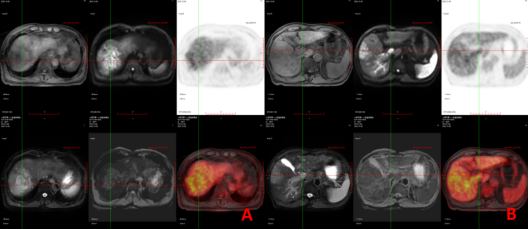

病例2PET/MR诊断原发性肝癌及癌栓A:肝右叶多发T1低信号T2压脂高信号占位,DWI为高信号,FDG代谢增高。B:门静脉主干及左右支稍增粗,T1低信号T2压脂高信号,DWI为高信号,FDG代谢增高。